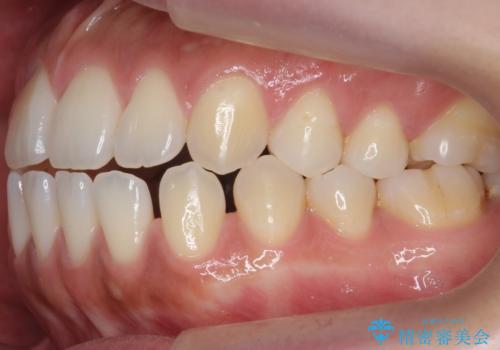

受け口、すきっ歯を インビザラインで モニター治療

- 前歯のすき間と受け口を気にして来院。

マウスピースでしっかり閉じています。

下の前歯を後方に移動するため、ゴムを上下のマウスピースにかけてもらいました。